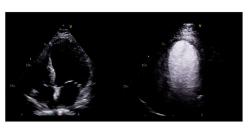

In der transthorakalen Echokardiografie zeigt sich eine deutlich eingeschränkte regionale Wandbewegung im Bereich aller apikalen Segmente im Sinne einer apikalen Akinesie, das übrige Myokard ist normal kontraktil. Die linksventrikuläre Ejektionsfraktion ist leicht reduziert (LVEF circa 45%). Im Apexbereich fällt eine echodichte, rundliche Struktur auf. In Zusammenschau mit der apikalen Akinesie besteht der hochgradige Verdacht auf einen linksventrikulären Spitzenthrombus (s. Abb. 2).

© Doctopia Abb. 2: Transthorakale Echokardiografie der vorgestellten Patientin, apikaler 4-Kammer-Blick. Es findet sich im linksventrikulären Apex eine runde echodichte Struktur (gestrichelter Kreis), in Zusammenschau mit der apikalen Kinetikstörung sehr gut vereinbar mit einem linksventrikulären Apex-Thrombus. RV = rechter Ventrikel, LV = linker Ventrikel, LA = linker Vorhof.

In diesem Fall war die Diagnose per konventioneller Echokardiografie zu stellen. Bei eingeschränkter Schallbarkeit kann es jedoch zu unklaren Befunden und Schallartefakten kommen. Hier hilft in vielen Fällen ein Ultraschallkontrastmittel zum Ausschluss von Thromben (s. beispielhaft Abb. 3). Nicht selten kann die Herzspitze durch technisch schwierige Schallbedingungen allerdings nicht darstellbar sein.

© Doctopia Abb. 3: Beispielhafte transthorakale Echokardiografie eines Patienten ohne Thrombus, apikaler 4-Kammer-Blick, linke Seite ohne und rechte Seite mit Linksherzkontrastmittel.